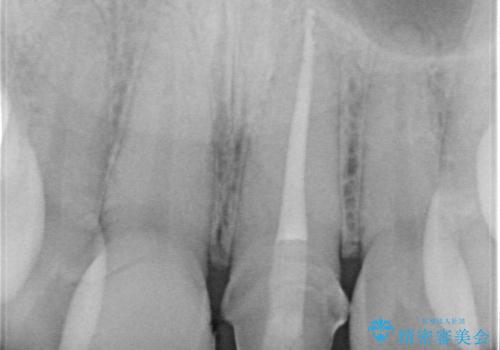

精密根管治療後、オールセラミッククラウンで治療を行いました。

治療後、違和感は無くなりました。

- 39.6万円(精密根管治療イニシャルケース11万円+ファイバーコア2.2万円+仮歯1.1万円×2+オールセラミッククラウンスタンダード12.1万円×2)費用は治療当時の料金となります

治療後、違和感が無くなり、被せ物で歯の長さが揃い見た目も改善されとてもご満足していただけました。